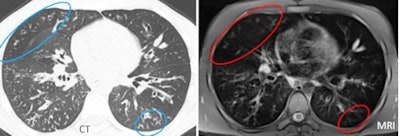

| MRI often overestimated mild disease, as in the case of a 24-year-old male patient with mild cystic fibrosis. In this patient, some small bronchiectasis of the right upper lobe (CT, left) appeared as a large area of mucus plugging (at MRI, right), resulting in an overestimation of the mucus score. This occurred because the wall thickening was blurred in the MR image, mimicking mucus plugs. |